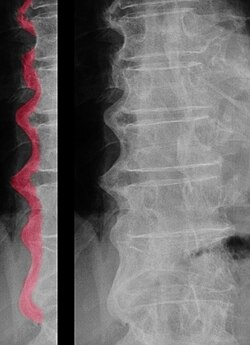

Skeletin diffuz idiopatik hiperostozu, Forestye xəstəliyi – qeyri-iltihabi xəstəlikdir, 50 yaşdan yuxarı, artıq çəkili və diabetli xəstələrdə olur, ən azı 4 ard

Skeletin diffuz idiopatik hiperostozu, Forestye xəstəliyi – qeyri-iltihabi xəstəlikdir, 50 yaşdan yuxarı, artıq çəkili və diabetli xəstələrdə olur, ən azı 4 ardıcıl fəqərənin ön boylama bağının kalsifikasiyası, qeyri-eroziv entezopatiyalarla gedir, AS fərqli olaraq sakroiliit, ankiloz və HLA-B27 pozitivliyi olmur